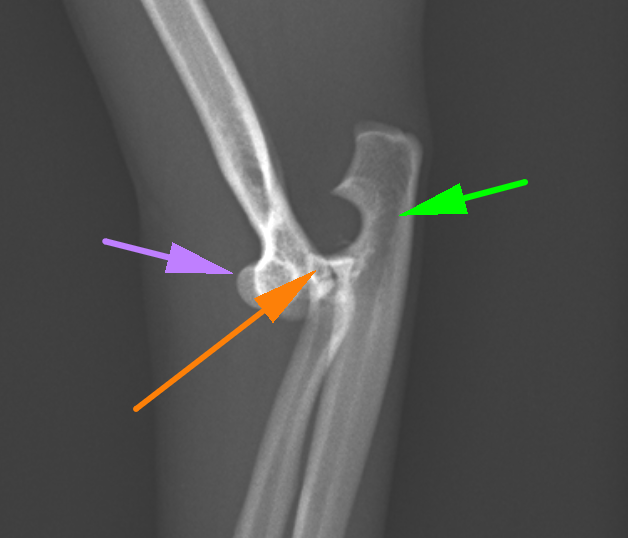

こちらが患肢の横から見たX線です。紫が上腕骨で、オレンジが橈骨、緑が尺骨です。このX線だと、上腕骨と橈尺骨が離れているのが分かると思います。橈骨と尺骨の脱臼はよくわかりません。